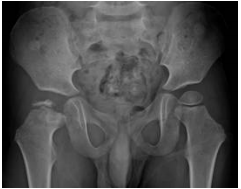

80 一位 5 歲好動男孩,近 3 個月來媽媽感覺他走路有漸漸嚴重的跛行,於診間檢查顯示他的右髖關節 外展(abduction)及內旋(internal rotation)活動有明顯受限,X 光如圖,男孩最可能罹患下列何種 疾病?

(A)過渡性髖滑囊膜炎(transient hip synovitis) (B)非特異性股骨頭缺血性壞死(idiopathic avascular necrosis) (C)感染性髖關節炎(septic arthritis) (D)股骨上端骨骺板滑脫(slipped capital femoral epiphysis)